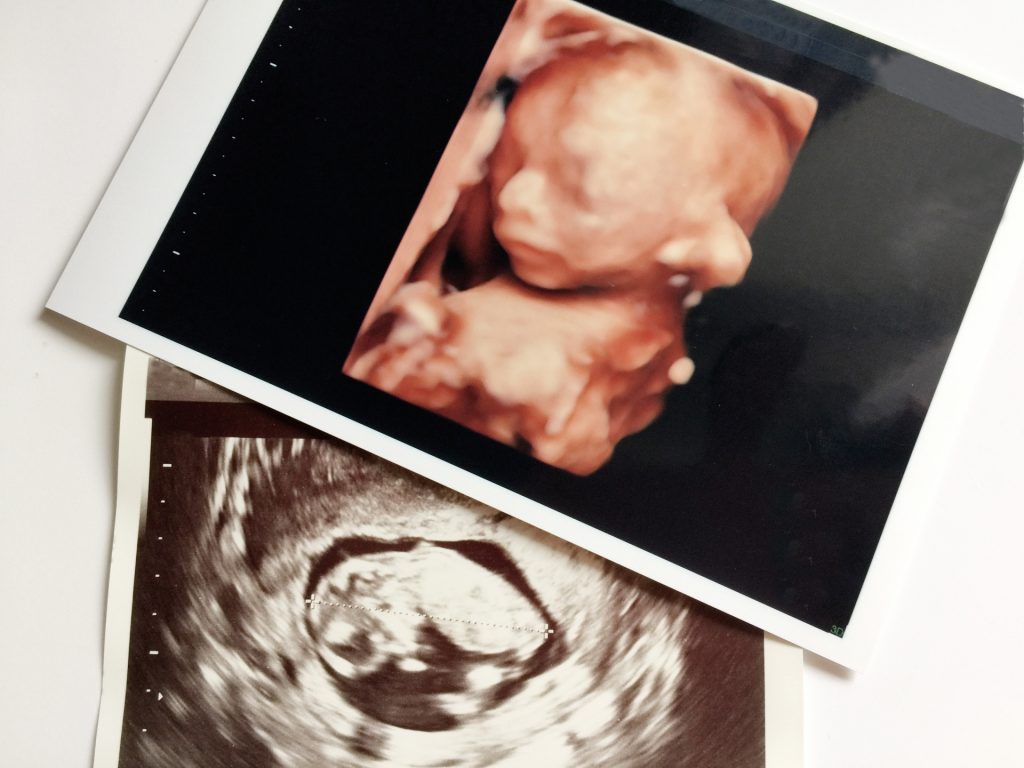

赤ちゃんがお母さんのお腹の中で育つ時、受精卵から分裂をくり返していろいろな臓器などができていきます。毛の組織である毛包もそのひとつ。

妊娠9週頃には毛包の発生は頭の方からはじまり、徐々におしりの方へとできていきます。

やがて妊娠4〜6ヶ月になる頃には、ほぼ全身に毛包ができあがっているそうです。だから生まれたての赤ちゃんにもちゃんと毛が生えているのですね。

妊娠3ヶ月頃には色素の元である「メラノサイト」のもとが表皮に移動してきます。これが毛球の上に来て、妊娠5ヶ月頃には胎児の毛が完成するのです。